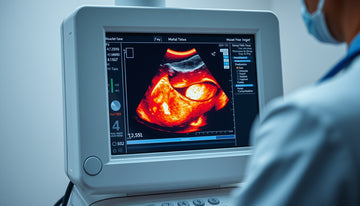

Ultrasound imaging is a diagnostic tool that utilizes high-frequency sound waves to create images of the structures within the body, particularly soft tissues. It is often ordered by licensed medical doctors when they deem it clinically appropriate based on the patient’s symptoms and physical examination. During the ultrasound, a trained technician applies a gel to the skin and then uses a transducer to emit sound waves, which bounce off the tissues and return data to generate images on a monitor. This imaging technique is particularly useful in visualizing soft tissues such as muscles, tendons, and ligaments, allowing for assessment of their appearance and movement. When ultrasound reports mention findings such as 'fatty infiltration of muscle,' they refer to the appearance of muscle tissue as seen on the ultrasound; any specific interpretation or significance of this finding relates to broader clinical assessments made by healthcare providers.

When an ultrasound report indicates 'fatty infiltration muscle,' it refers to an observation regarding the appearance of muscle tissue in the imaging results. This terminology suggests that there may be an increased presence of fat within the muscle compared to typical muscle composition. Ultrasound is particularly useful in visualizing soft tissues, including muscles, by assessing their structure and movement. It is important to understand that while this finding may be reported, it does not provide any direct information about an individual's pain levels or functional capacity. The interpretation of such results should always be conducted by a licensed medical professional, who will contextualize these findings within the larger picture of the patient's health and activity. Further, discussions around long-term support for muscles and connective tissues may arise, as some individuals consider various approaches for maintaining normal structure and function alongside professional care.